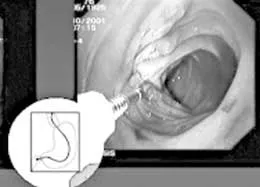

Vai trò H. Pylori trong loét dạ dày tá tràng ảnh 1

Những người trên 45 tuổi nên xét nghiệm tìm H.Pylori khi: rối loạn tiêu hóa, giảm cân, xuất huyết, thiếu máu, khó nuốt. Ảnh: Tìm H.Pylori trong tá tràng

Chẩn đoán HP hiện nay có 2 phương pháp: xâm lấn và không xâm lấn. Phương pháp xâm lấn là phải nội soi dạ dày- tá tràng, qua đó người ta lấy một mẫu mô của dạ dày đem thử xem có HP không? Thử mô học (giải phẫu bệnh) giúp xác định loét và loại trừ bệnh lý ác tính của dạ dày.